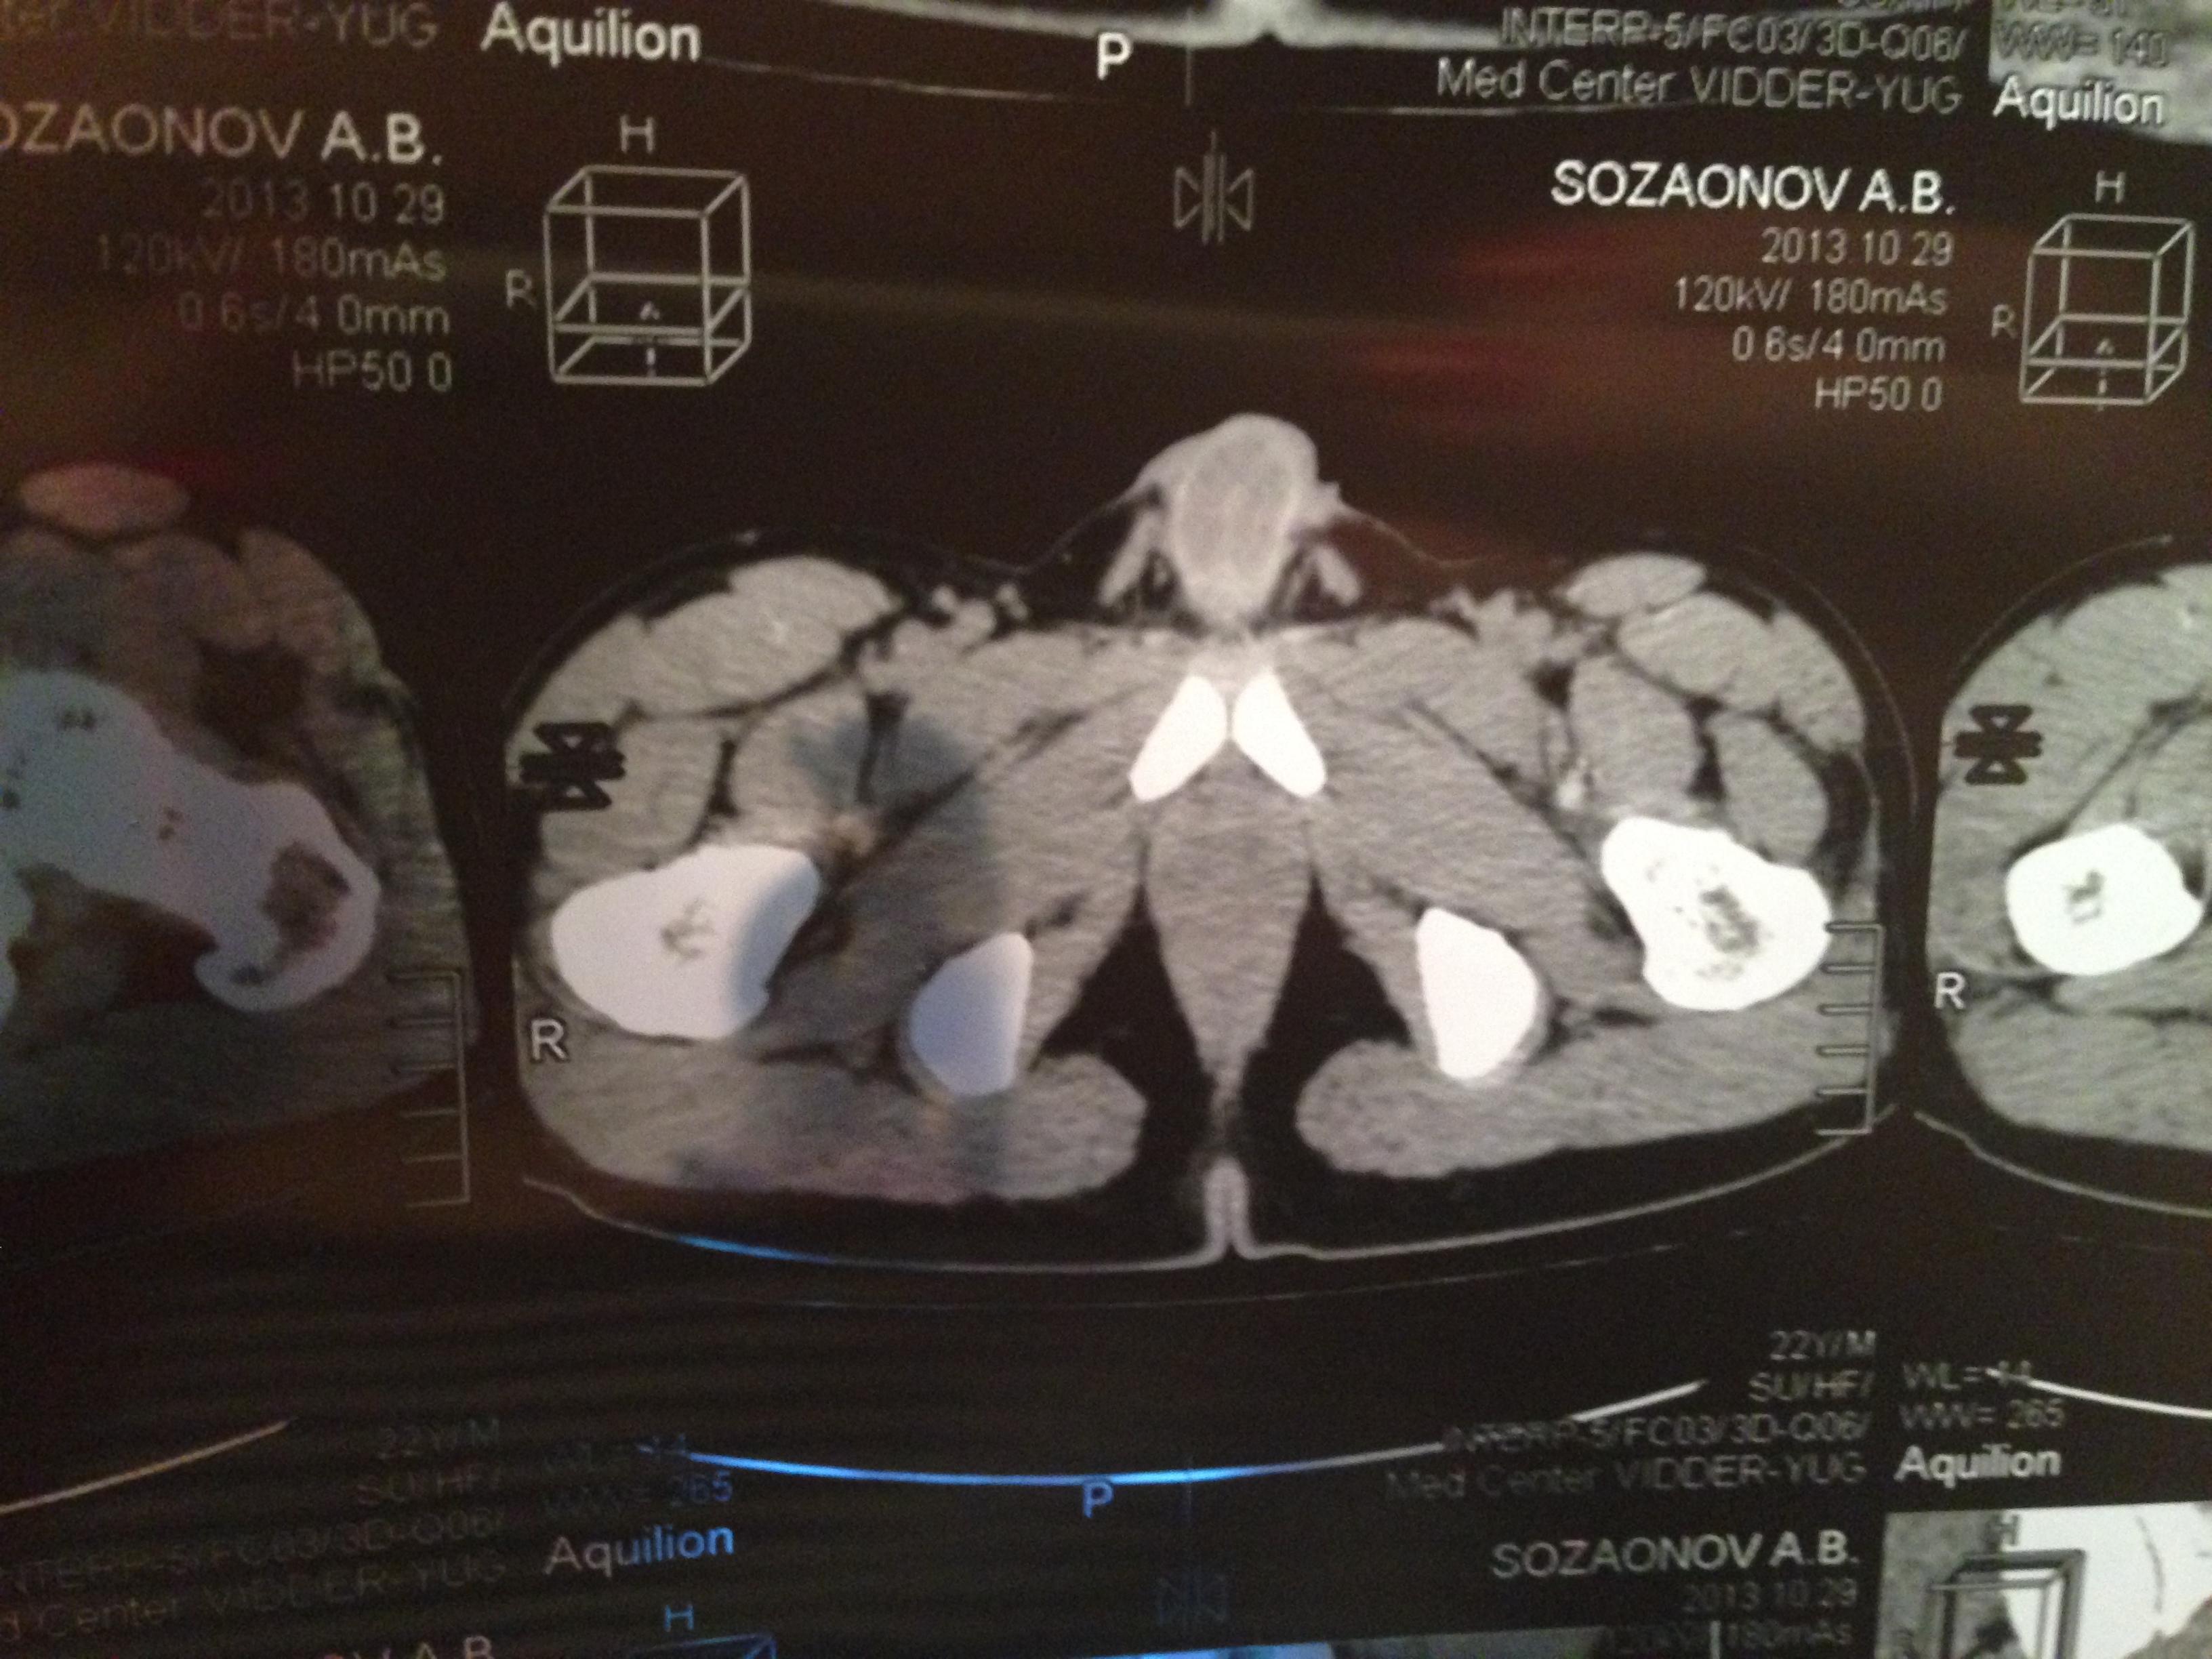

проведена МСКТ области таза!Внеорганных дополнительных патологических образований,лимфаденопатии или свободной жидкости в области таза не выявлено.

Мочевой пузырь-наполнен,стенки не утолщенны,паравезикально-без грубой органки.

Граница между предстательной железой и пузырем несколько четкая,контур пузыря на данном уровне не деформирован.

Предстательная железа-без грубой органики,еденичные микрокальцинаты.

Семенные пузырьки-конфигурация не совсем типична,примерный размер правого 26*28мм.Отмечаются признаки кистовидной трансформации и микрокальцинации обоих пузырьков.Наибольшая из кист слева достигает 9 мм.Обращает на себя внимание неравномерная кальцинация стенок крупных регионарных(текстикулярных)артерий с обоих сторон.

Костно-деструктивных изменений характерных для mts со стороны костей таза не отмечено.

Параректальная клетчатка-не изменена,патологически увеличенных лимфоузлов в параректальном пространстве не отмечено.M.m.levator ani-без особенностей.

Заключение:на момент исследования,КТ-данных за наличие внеорганных дополнительных патологических образований,лимфоденопатии или свободной жидкости в области таза не выявлено.КТ-признаки в пользу проявлений калькулезного везикулита с элементами кистовидной трансформации семенных пузырьков.